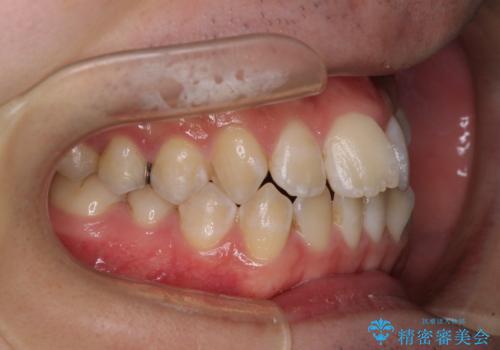

- 上下前歯のデコボコを気にして来院された患者様です。

ワイヤー矯正でもマウスピース矯正でも可能でしたが、短期間で、自身の手を煩わせることなく治療を行いたいとのことで、ワイヤー装置にて矯正治療を行うこととしました。